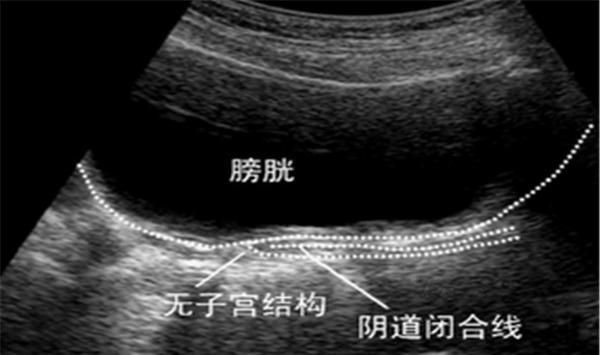

很多女性都会很憧憬自己的第一次,浪漫、温馨,因为爱所以选择在一起。不过对极少数女性来说,这样的憧憬都是一种奢望,就是因为“石女”,民间称之为“石芯子”,是指无法正常行经、无法性生活的女性。造成“石女”的原因包括处女膜闭锁、阴道横膈,这两类女性的阴道及其他生殖器官发育良好,而阴道闭锁或先天性无阴道是由于生殖系统发育不完全。

图片来源:网络搜索

石女分为“外石”和“内石”,“外石”也称“假石”,是指由于处女膜肥厚或闭锁,无法顺利进行性生活,这种情况进行处女膜切开手术即可治疗,术后能过正常的性生活;

“内石”,也称“真石”,则指先天性无阴道,这是由于胚胎时期发育成子宫和阴道的苗勒氏管未腔化所致。

“真石”是因为胎儿期生殖器官发育异常停滞,“假石”则与后天发育相关。

要知道的是,这种先天缺陷并非一出生就能被发现,有的人是到青春发育期迟迟不来月经赴院检查后发现,有的人则是在你侬我侬时无法顺利进行性生活发现的。

不过是有极少数女性是真正缺少阴道的,即无阴道也无子宫,既不能来月经,也无法怀孕生孩子,医生可通过手术恢复一些性生活的能力,却没办法恢复月经和生育能力;

有无阴道的女性却有发育正常的子宫,可以产生月经,但无法排出去,形成与处女膜闭锁相似的症状,该类情况应在初潮年龄进行手术。如果经血不能顺利排出,血液在阴道内集聚,流到子宫,积血过多可流入输卵管,通过伞部进入腹腔,伞部附近的腹膜受经血刺激发生水肿,长期以往,可能会诱发炎症,造成骨盆组织粘连、感染等。

总而言之言而总之,无论是哪种情况,在初潮到来之前,很少有人能够注意到这一问题,大多是青春期后长期未来月经或性行为无法进行时才被发现。所以,新生儿的生殖系统检查也就尤为重要。不过现如今,大多数“石女”可以通过外科手术来治疗,较于相对严重的先天性,治疗方法也日渐成熟。

另外值得注意的是,在绝大多数情况下,处女膜或阴道的异常现象对于女性的第二性征没有什么影响。性腺的发育受到原生殖细胞和生殖嵴的影响,而阴道的发育则是由副中肾管、泌尿生殖窦以及阴道板发育形成的。因此,阴道、处女膜以及子宫的异常并不会影响卵巢的发育,因而不会影响雌性激素的分泌。